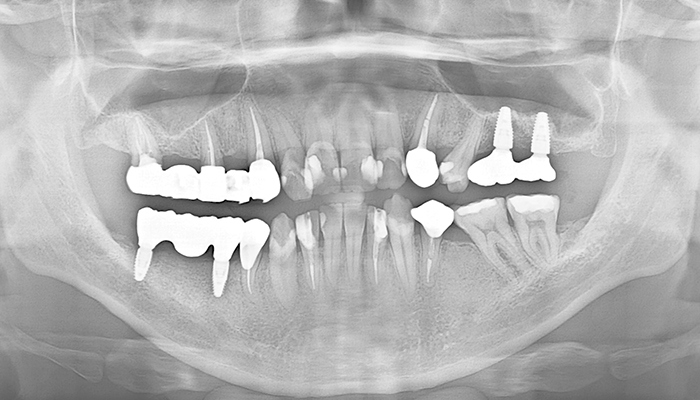

【30代女性】

前歯2本以上のインプラント症例

「転倒して前歯2本を失った方」

治療前

治療後

インプラント埋入直後

仮歯

| 主訴 | 事故で怪我したため、欠損した箇所を治したい |

|---|---|

| 治療期間 | 約5ヶ月 |

| 治療費 | 1本あたり350,000円(税別)×2本 合計2本70万円(税別) |

| 治療内容 | 前歯のインプラント治療 |

| 治療のリスク | 前歯のインプラント治療では、審美性の問題や骨密度不足によるインプラントの不安定、神経損傷や感染のリスクがあり、術後の腫れや痛みも発生する可能性があります。 |